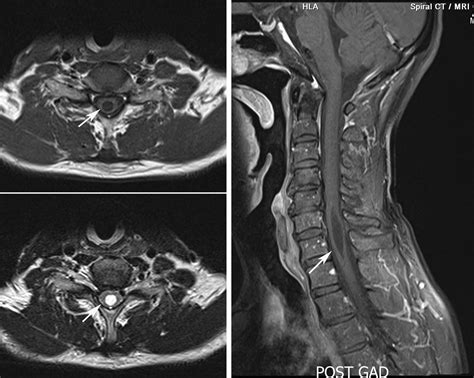

• normal cervical mri without contrast

• normal cervical mri axial

• normal cervical mri sagittal view